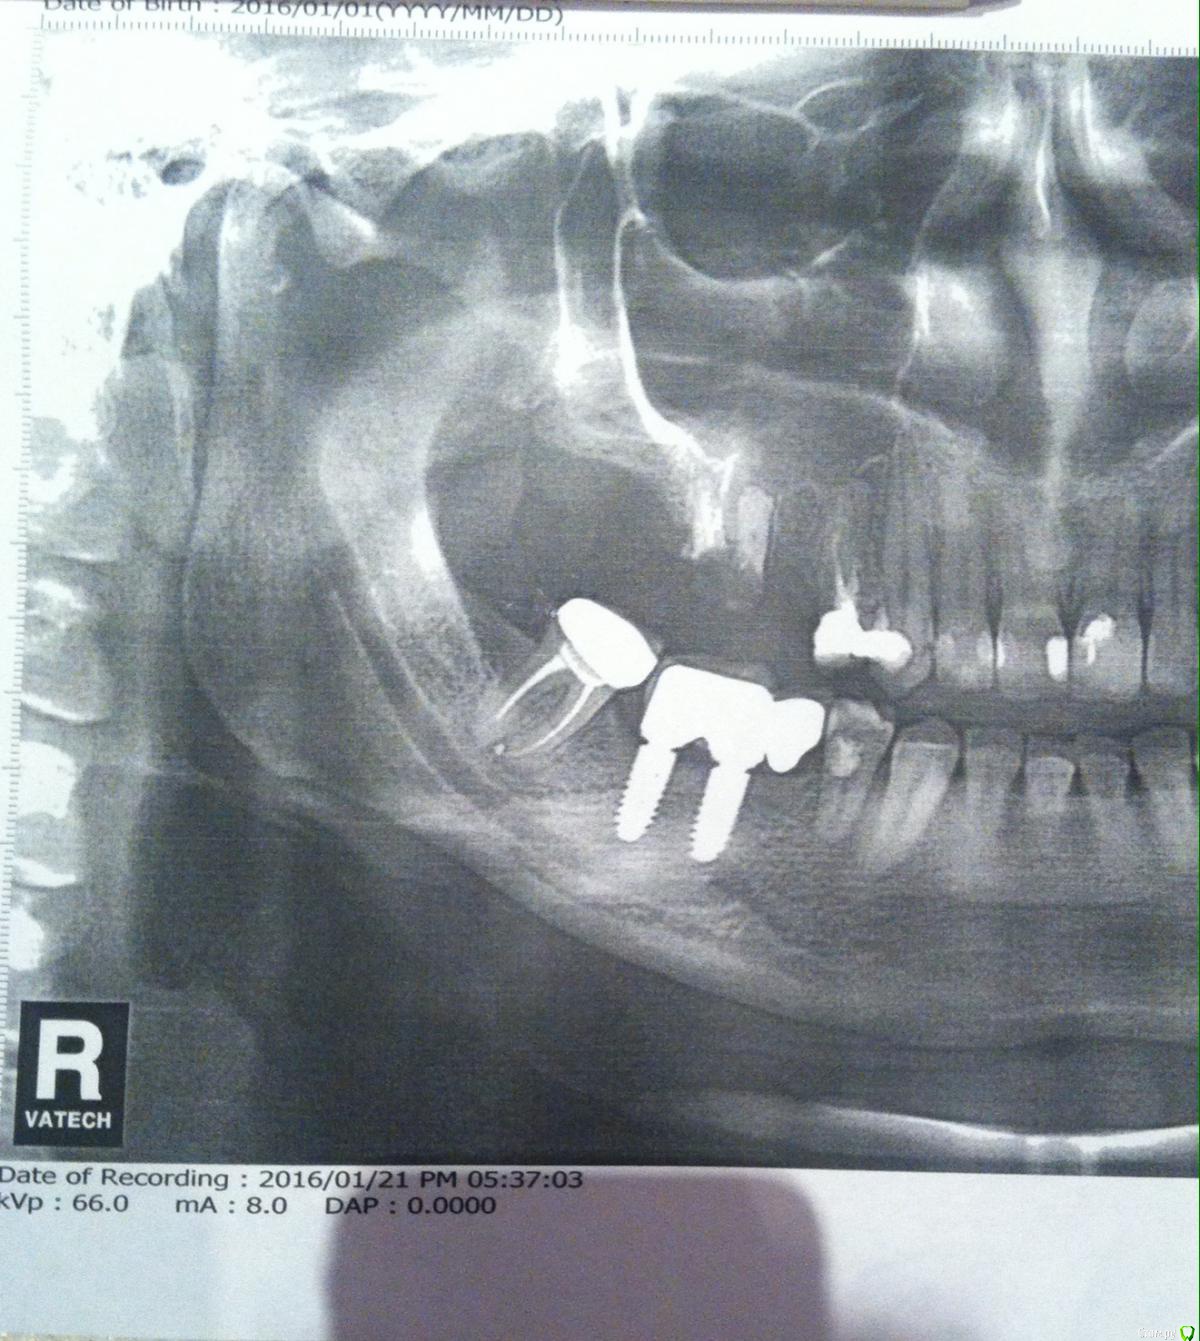

T.blondinka Опубликовано 26 января, 2016 Автор Поделиться Опубликовано 26 января, 2016 Спасибо! Мне ж еще и два импланта "вкрутили"... Ссылка на комментарий

T.blondinka Опубликовано 31 января, 2016 Автор Поделиться Опубликовано 31 января, 2016 К сожалению, этот снимок-все что есть из об. данных. Киста нашлась на 6-ом сейчас уже удаленном корне зуба (верх. челюсть). Импланты сверху на месте пятого и шестого зуба. Даже название и длину "саморезов" не знаю. На осмотре после ОП не была, доктор заболел. Ем Амоксиклав 625 -7 дней, 1т 2р, Ибупрофен-5 дней, 1т 2р, капли в нос Тизин 2-3р 7 дней, мазала три дня утром и вечером Солкосерил, но от мази потом полдня отплевываться приходилось(((... Купила Метрогил Дента, надеюсь что на общий процесс заживления это не сильно повлияет... Первые несколько дней была небольшая температура, отек - прошло. Остался желтый синяк. Немного подкравливает десна, а сегодня уже пятый день после ОП Ссылка на комментарий

Bier Опубликовано 1 февраля, 2016 Поделиться Опубликовано 1 февраля, 2016 Прошу прощения за глупый вопрос, но все же я его задам. А как кость наращивать, если уже вкрутили имплант на место удаленного корня зуба с кистой?ну значит хирург нашел кость для размещения имплантата. Нужно смотреть снимок после имплантации. 1 Ссылка на комментарий